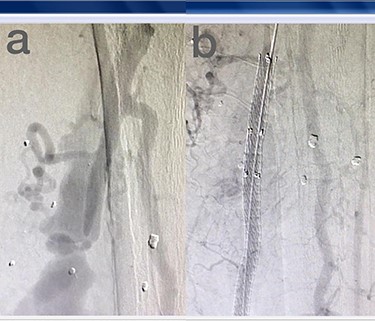

Sites of injury included 6 Posterior Tibialis arteries (27.2%) (Fig. 1), 2 deep femoral arteries (9.09%), 2 Superficial femoral arteries (9.09%) and 2 maxillary arteries (9.09%). We had only one injured artery (4.54%) in each of the following sites: internal pudendal a., Axillary a. (Fig. 2), Proneal a., Lumbar a., External carotid a., Anterior Tibialis a., common iliac a. (Fig. 3), temporal a., Thoracic aorta and Internal iliac artery (Fig. 4).

(a) Common iliac artery before intervention, (b) after stent-graft deployment.